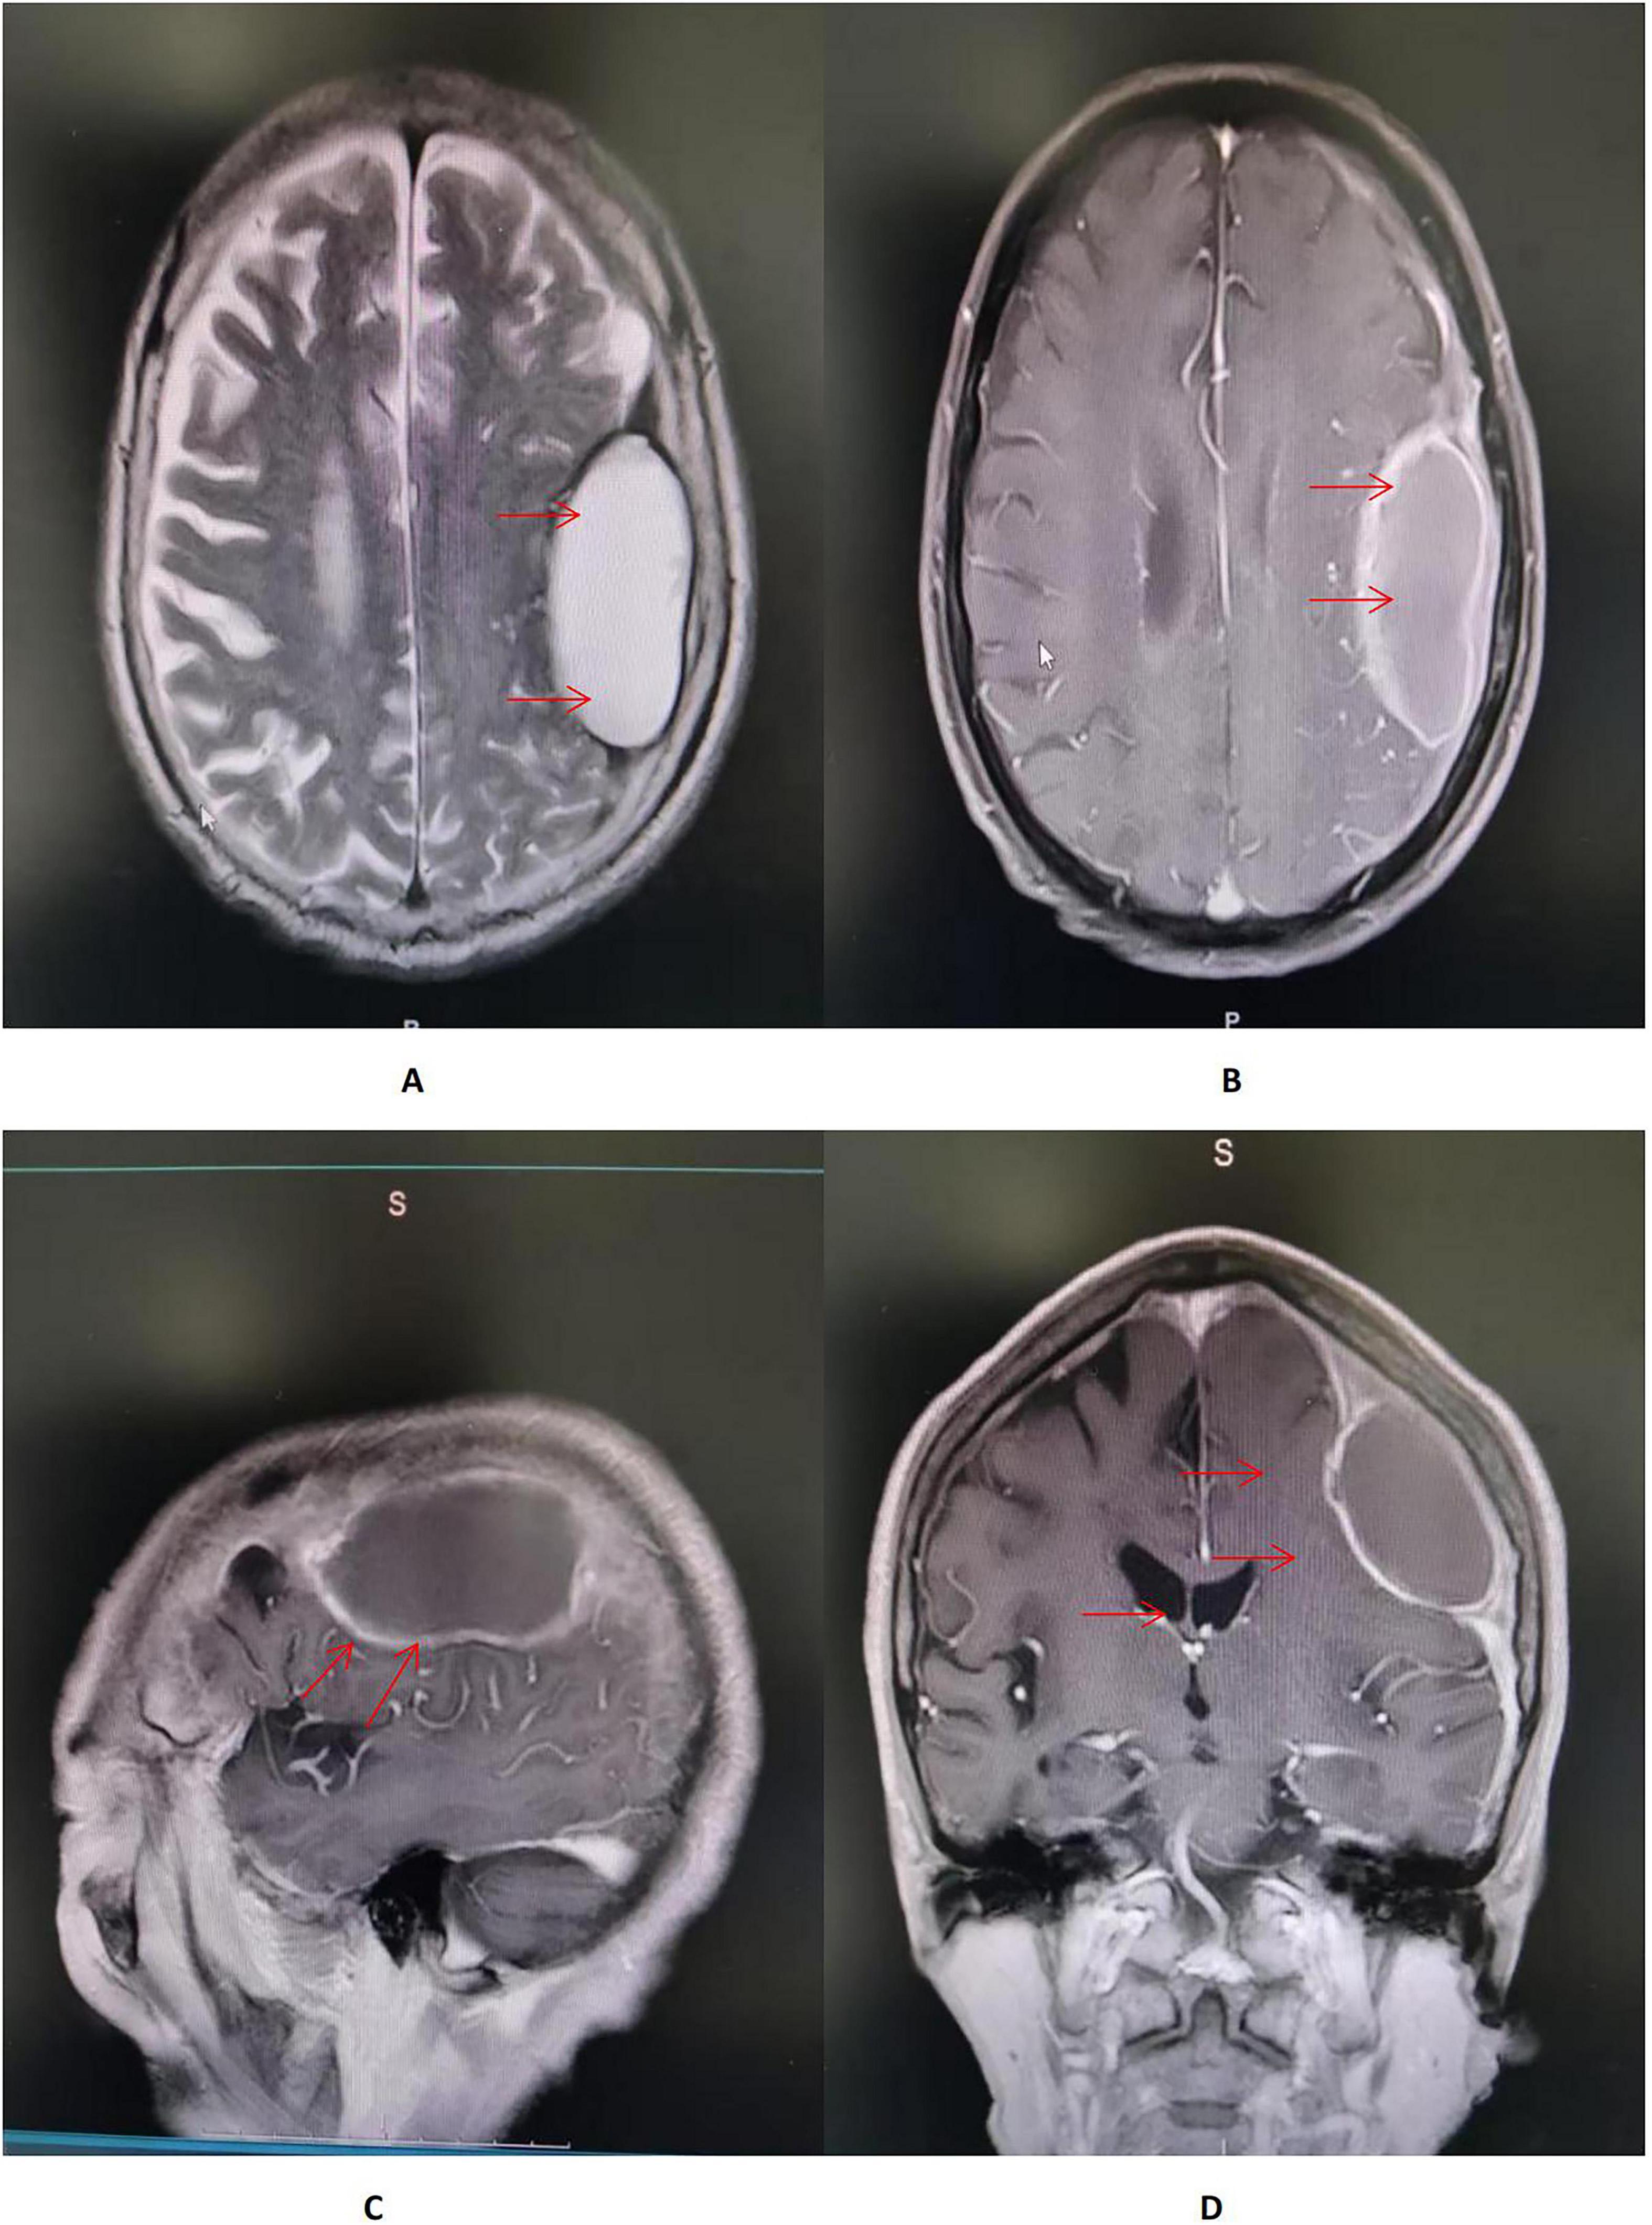

On hospital day 7, axial T2-weighted/FLAIR and T1-weighted MRI of the head demonstrate a mass-like abnormal signal focus in the left frontoparietal region, measuring approximately 31 mm × 58 mm. The lesion appeared hyperintense on T2-weighted/FLAIR images and iso- to hypointense on T1-weighted images. A significant perilesional edema was present in coronal contrast-enhanced T1-weighted MRI, causing mild mass effect and displacement of the surrounding brain structures (Figure 2). Spinal MRI showed no abnormal signal intensity suggestive of involvement (Figure 3). Lumbar puncture was immediately performed. Opening pressure was elevated at 220 mmH2O, and the CSF appeared turbid. Routine CSF analysis (Table 1) demonstrated: white blood cell (WBC) count 460/mm3, Pandy’s test positive, total protein 1312 mg/L, glucose 0.99 mmol/L, chloride 115.9 mmol/L, and a standard tube agglutination test (SAT) titer of 1:480. Metagenomic next-generation sequencing (mNGS) of the CSF detected 3489 sequence reads of Brucella melitensis. The diagnosis was revised to neurobrucellosis (meningitis) complicated by giant intracranial abscess formation. Simultaneously, we cultured the cerebrospinal fluid on Columbia blood agar plates at an ambient temperature of 35 degrees Celsius. Following the current Chinese guidelines for neurobrucellosis (10), antimicrobial therapy was intensified with the addition of ceftriaxone (2 g every 12 h). Mannitol (125 mL every 8 h) was initiated for intracranial pressure reduction, and dexamethasone (10 mg once daily) was added to mitigate inflammatory exudation. Subsequently, the patient’s headaches began to subside.

FIGURE 2

(A,B) Axial T2-weighted/FLAIR and T1-weighted MRI of the head demonstrate a mass-like abnormal signal focus (red arrow) in the left frontoparietal region, measuring approximately 31 × 58 mm. The lesion appeared hyperintense on T2-weighted/FLAIR images and iso- to hypointense on T1-weighted images, situated immediately beneath the inner table of the skull. A moderate perilesional edema was observed, with localized effacement of adjacent sulci. No significant midline shift was identified. (C) Sagittal contrast-enhanced T1-weighted MRI of the head showed an in homogeneously enhancing lesion in the left frontoparietal region, abutting the dura mater with a prominent “dural tail sign” (red arrow). The lesion had well-defined margins, and the surrounding edema showed no enhancement. (D) Coronal contrast-enhanced T1-weighted MRI of the head demonstrated a large mass lesion with rim enhancement and a non-enhancing central area, suggestive of cystic or necrotic components. A significant perilesional edema was present, causing mild mass effect and displacement of the surrounding brain structures (red arrow).

Imaging plays a significant role in the diagnosis and differential diagnosis of neurobrucellosis. Neurobrucellosis can present with four types of imaging findings: normal appearance, inflammatory changes characterized by abnormal enhancement, white matter changes, and vascular changes. Inflammatory changes can manifest as either diffuse, primarily leptomeningeal enhancement, or focal inflammatory lesions, including encephalitis/myelitis, nerve root enhancement, granulomas, and abscess formation (39). However, imaging features of Brucella brain abscesses are rarely reported, and whether they possess specific inflammatory changes remains inconclusive. Our case provides a reference: MRI showed meningeal thickening, a ring-enhancing lesion with no enhancement in the central necrotic area of the abscess, and surrounding edema of varying degrees. Its imaging appearance is similar to brain abscesses caused by other bacteria, necessitating thorough correlation with microbiological results for diagnosis.